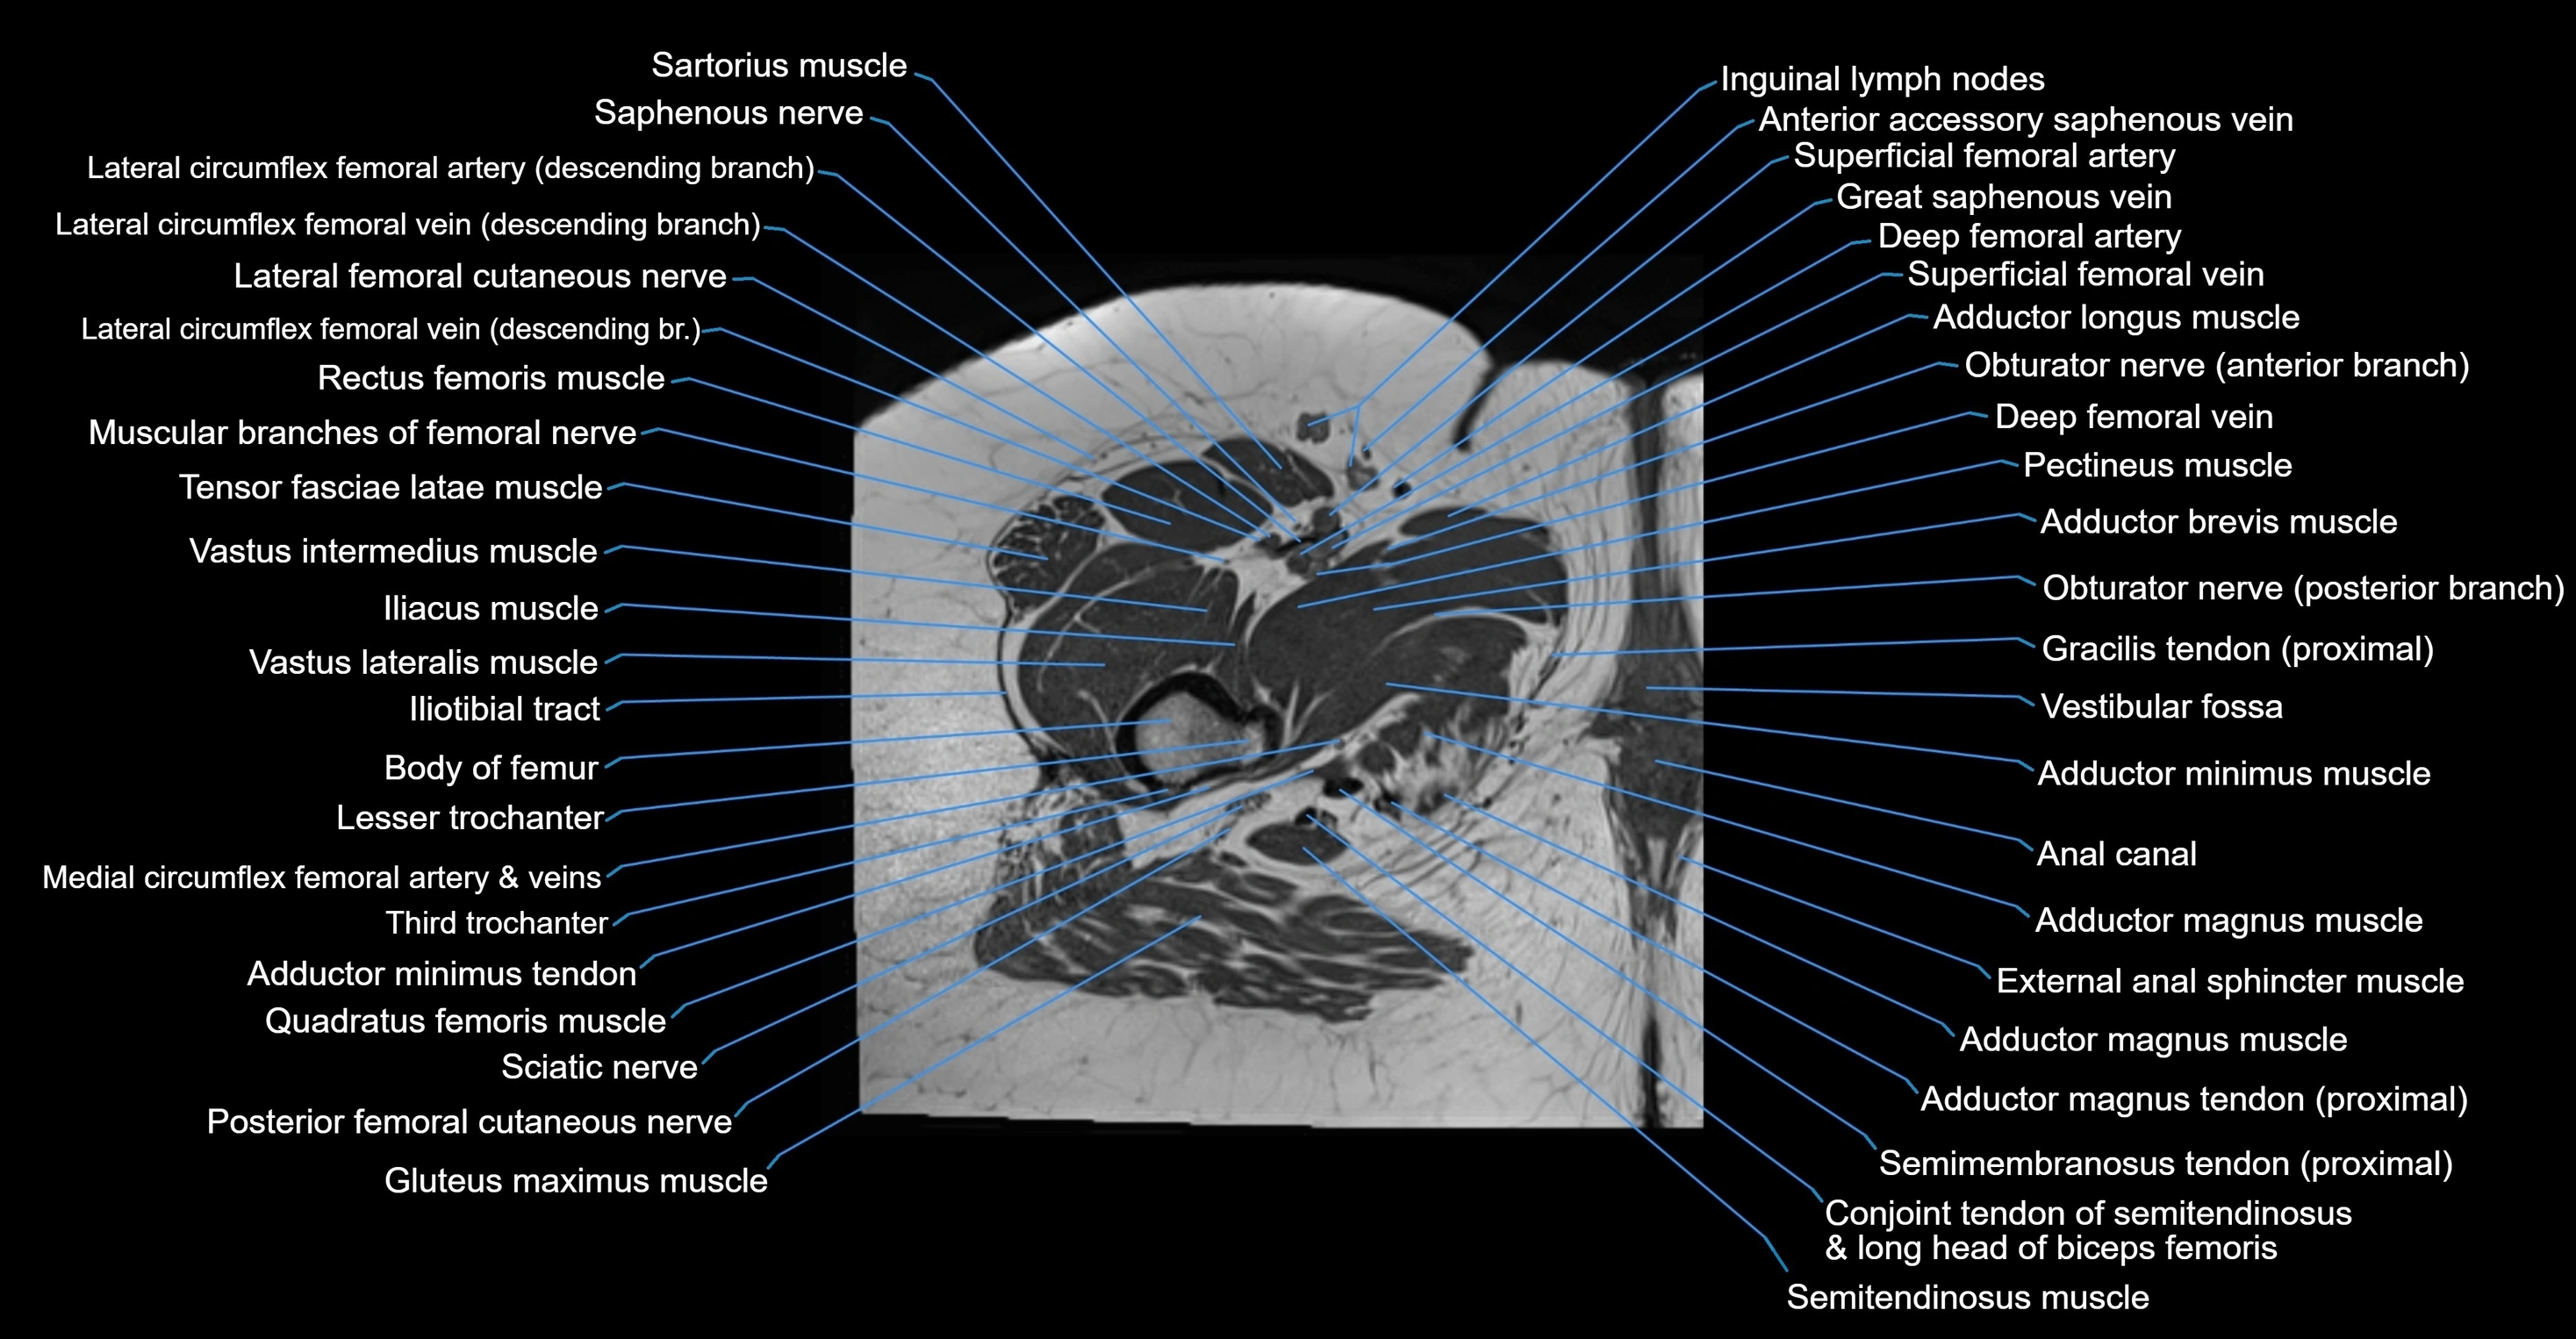

- Adductor brevis muscle

- Adductor longus muscle

- Adductor magnus muscle

- Adductor minimus muscle

- Anal canal

- Conjoint tendon of biceps femoris & semitendinosus

- Femoral nerve

- Gluteus maximus muscle

- Iliotibial tract

- Inguinal lymph nodes

- Lateral femoral cutaneous nerve

- Lesser trochanter

- Muscular branches of femoral nerve

- Pectineus muscle

- Posterior femoral cutaneous nerve

- Quadratus femoris muscle

- Sartorius muscle

- Semimembranosus tendon (proximal)

- Tensor fasciae latae muscle

- Third trochanter

- Vastus intermedius muscle

- Vastus lateralis muscle

- Vestibular fossa